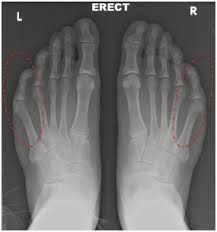

Der kleine Zeh ist dabei im Zehengrundgelenk abgeknickt und verursacht wie der Hallux valgus eine Exostose Überbein am Grundgelenk die sich schmerzhaft entzünden kann Bursitis. Bei einem Brennen in den Zehen empfinden die meisten Patienten ein schmerzhaftes Kribbeln in den Zehen ähnlich dem Gefühl eines eingeschlafenen Fußes. Kommt es zu Schmerzen im Zeh sollte geprüft werden ob die getragenen Schuhe den Zehen ausreichend Platz geben.